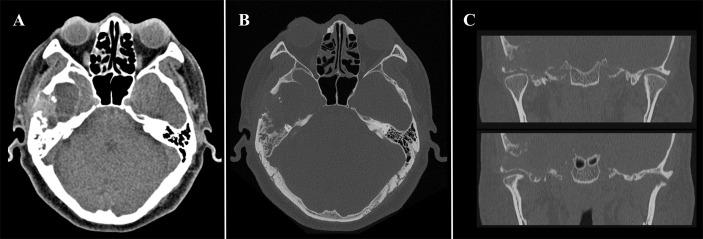

Diffuse tenosynovial giant cell tumor (D-TSGCT) is a benign but locally destructive tumor of synovium that may involve joints, tendon sheaths, and bursae. Its occurrence in the temporomandibular joint (TMJ) is extremely rare. The authors reported a case of 48-year-old man with an extra-articular D-TSGCT in the TMJ with medial cranial fossa extension. computed tomography (CT) and magnetic resonance imaging (MRI) features are described. The lesion was a cystic-solid mass centered at the temporal bone without involvement of the condylar head, and its solid component presented high-density on CT and hypointensity on MRI. No signs of recurrence or metastasis was observed during 12-months of follow-up. The present report suggested the potential characteristics of radiologic imaging of D-TSGCT in TMJ.

弥漫性腱鞘巨细胞瘤(D-TSGCT)是一种起源于滑膜的良性但具有局部侵袭性的肿瘤,可累及关节、腱鞘和滑囊。其发生于颞下颌关节(TMJ)极为罕见。作者报告了一例48岁男性,患有颞下颌关节的关节外D-TSGCT并向颅中窝扩展。描述了计算机断层扫描(CT)和磁共振成像(MRI)特征。病变为以颞骨为中心的囊实性肿块,未累及髁突头部,其实性成分在CT上呈高密度,在MRI上呈低信号。随访12个月期间未观察到复发或转移迹象。本报告提示了颞下颌关节D-TSGCT的放射学成像潜在特征。